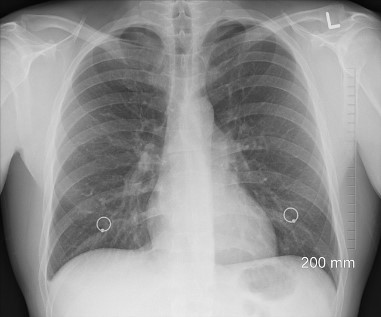

기흉은 흉부 내부의 공기가 비정상적으로 폐 외부로 누출되는 상태를 말합니다. 폐에 구멍이 나면 폐의 압력이 가슴속의 압력과 같아져서 사슴 속의 부피에 따라 폐가 커지거나 작아지지 못하므로 공기가 폐로 나가지 못하게 되어 호흡곤란이 일어납니다.

일반적으로 기흉은 두 가지 유형으로 첫 번째는 외상성 기흉으로 외상이나 부상으로 인해 폐에 손상이 생기면서 기흉이 발생하며, 찔린 상처, 강한 타격, 골절 등이 이에 해당합니다. 그리고 두 번째는 비외상성 기흉으로 원발성 비외상성 기흉 (어떤 명확한 원인 없이 발생하는 기흉입니다. 주로 젊은 청년들에게서 발생하며, 기저에는 폐 조직의 기포나 낭종 등이 있을 수 있습니다.)과 이차성 비외상성 기흉(기저에 기저질환이나 손상이 있는 경우에 발생하는 기흉입니다. 폐 질환, 폐종양, 천식, 감염 등이 이에 해당합니다.)으로 유형이 나눠집니다.

기흉이 발생하면 폐의 일부 또는 전체가 흉강으로 이동하게 됩니다. 기흉은 폐와 흉강 사이의 압력 차이로 인해 발생할 수 있습니다.